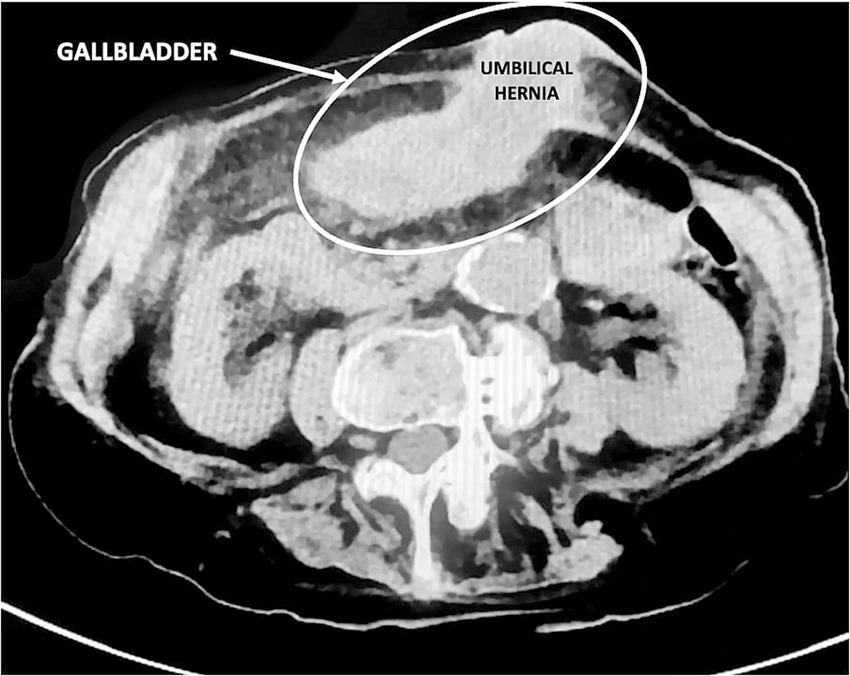

Figure 2

Preoperative CT scan clearly revealed what was later identified as the gallbladder within the umbilical hernia.

In March 2023, a 97-year-old woman was hospitalized for 20 days in the General Medicine Department of our Hospital due to suspected urinary sepsis, supported by positive urinalysis and urine culture findings. Despite her advanced age, the patient was in fair overall clinical condition. She was 151 cm tall, weighed 47 kg (body mass index 20.6 kg/m2), and had a medical history of hypertension, osteoporosis, bronchial asthma, and asymptomatic umbilical hernia. The patient also had a documented history of cholecysto-choledocholithiasis; however, no prior surgical or endoscopic treatments were documented, and detailed information regarding previous management was unavailable. During her hospital stay, she was successfully managed conservatively with antibiotic therapy. However, given the presence of initial nonspecific abdominal symptoms, a computed tomography (CT) scan was also performed. Findings excluded the presence of surgical emergencies, with the only abnormality being a distended gallbladder positioned in the mesogastric region, with mildly thickened walls (Figure 1). However, on clinical examination Murphy and Blumberg signs were negative. Despite radiological suspicion of mild cholecystitis, her advanced age and post-antibiotic clinical improvement led to her being deemed clinically stable and discharged. Two weeks later, the patient presented to the Acute Care Department with new-onset abdominal pain in the periumbilical region. On clinical examination, a tender mass approximately 4 cm in diameter was noted in the umbilical area, with visible redness of the overlying skin. Laboratory tests showed neutrophilic leukocytosis (13.7 × 109/L) and elevated C-reactive protein (103 mg/L). Hemoglobin was within the normal range (12.4 g/dL), as were total bilirubin (0.8 mg/dL) and liver enzymes, including transaminases, alkaline phosphatase, and gamma-glutamyl transferase. A mild renal impairment was also noted, with serum creatinine slightly above the normal range (1.3 mg/dL), and blood urea modestly elevated (7.9 mmol/L). Lactate levels were slightly elevated at 2.4 mmol/L. Due to the clinical presentation and laboratory findings a contrast-free CT scan was performed (Figure 2). The radiological report described a strangulated bowel loop within a 3-cm umbilical orifice. Nevertheless, the gallbladder enlargement noted on the prior CT scan left open the possibility of its involvement. Urgent surgical intervention under general anesthesia was therefore planned. A lower midline laparotomy, far from the hernia site, was initially performed to avoid visceral injuries. The incision was then extended cranially. Intraoperative findings excluded bowel ischemia, while revealing the presence of acute cholecystitis (Figure 3): a huge gallbladder was found twisted along its longitudinal axis, with inflamed and fragile but intact walls, including the fundus, which was strangulated within the hernial orifice. The hernial neck was resected first to avoid gallbladder rupture and prevent contamination of the operative field. Following careful dissection, an anterograde cholecystectomy was carried out. Furthermore, given the abnormal dilation of the common bile duct (2 cm) and the patient’s known history of cholecysto-choledocholithiasis, a longitudinal choledochotomy was also performed. Intraoperative choledochoscopy using a flexible choledochoscope revealed a large 2 cm gallstone partially obstructing the distal common bile duct, in close proximity to the ampulla of Vater. The stone was successfully extracted using forceps, and a T-tube was subsequently placed for biliary drainage. Finally, hernia repair was completed with primary abdominal wall closure. The postoperative course was complicated by the onset of pneumonia on postoperative day 4, which was successfully treated with a penicillin. A bile leak was also revealed by the subhepatic surgical drain. The patient was discharged on postoperative day 14 in fair overall clinical condition, with the T-tube left open, draining approximately 200 cc per day, while the surgical drain output was around 50 cc per day. After discharge, the bile leak gradually decreased, leading to the T-tube being clamped 1 month later. Subsequently, the surgical drain was removed, while the T-tube was taken out 3 months after surgery without complications, following a control cholangiography. Histological examination revealed acute empyematous cholecystitis. The patient was subsequently evaluated in the outpatient clinic every 6 months until the last follow-up in February 2025, at which time she was alive and in a stable overall condition. Figure 4 show the case presentation timeline.